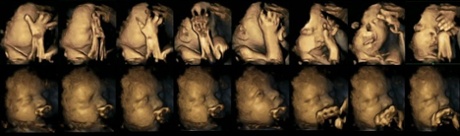

fetus womb smoking mom

Scans showing a sequence of movements displayed by two fetuses at 32 weeks’ gestation. The image shows fetal movements in a fetus whose mother is a smoker (top) and a fetus whose mother is a non-smoker (below). Photograph: Durham University

In the scans released with the study, fetuses of the smoking mothers appear to be almost covering their faces.